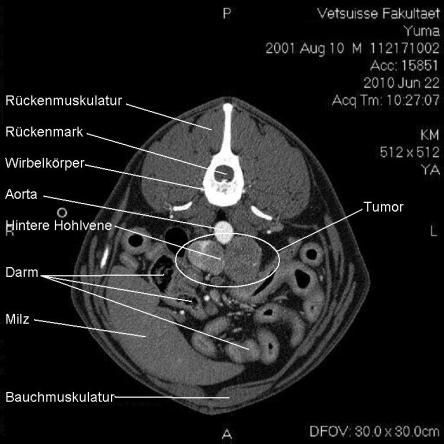

Computertomogramm

Die Computertomographie (CT) liefert mittels eines röntgenähnlichen Verfahrens ein dreidimensionales Bild des untersuchten Körperteils. Da das untersuchte Tier vollständig ruhig liegen muss, wird Yuma zur Untersuchung narkotisiert.

Im CT wird ersichtlich, dass sich der Tumor, welcher von der linken Nebenniere ausgeht, schon sehr weit in das Gefässystem von Yuma vorgearbeitet hat. Krebsausläufer finden sich wie erwartet in der Hohlvene, aber auch in der Nierenvene sowie in einer weiteren grossen Vene. Der Geschwulst ist somit inoperabel.